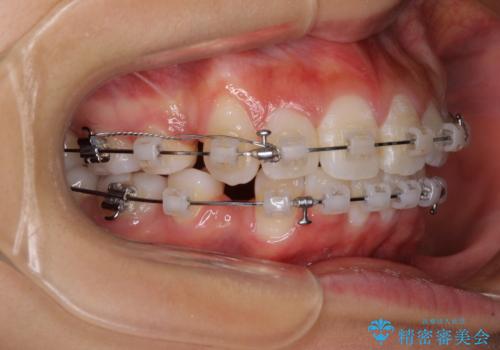

- クリアブラケット

- 1年7ヶ月

口元の突出感を改善するため、上下左右第一小臼歯4本の抜歯を行い、ワイヤー装置による矯正治療を行うこととしました。

治療前の上下正中はずれていましたが、骨格的な上下左右差はあまり認められなかったため、正中を揃えて治療を終えることができました。